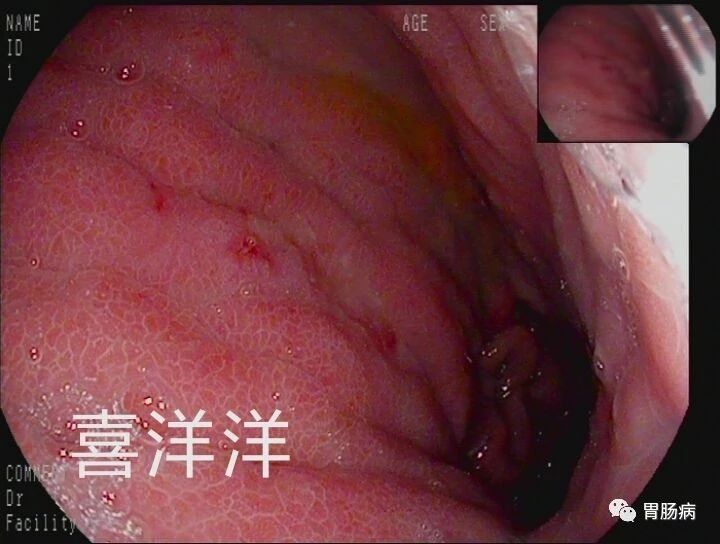

当时胃镜检查也没有发现明显的问题,而且医生还取了活检,病理报告也是慢性炎症,并没有什么特别的情况。于是医生按照慢性胃炎和消化不良给开了一些胃药。

医生告诉他,虽然胃镜是金标准,但并不是100%不会漏诊,尤其是对于一些特殊类型的胃病。

而印戒细胞癌却是向胃壁外面生长,在早期,甚至在进展期,在胃粘膜表面并没有明显的改变,所以很容易漏诊。

本病早期并无明显症状,甚至胃黏膜也没有任何改变,很多首次胃镜会被诊断为浅表性胃炎!

虽然本病在早期难以发现,但并非不能发现。东方医院的曹佳医生曾在1个月内,就发现了3例胃早期印戒细胞癌。

均是没有任何典型症状来做例行胃肠镜检查,均为女性,病变均为黏膜内癌,发现难度极大,需要丰富的内镜经验与先进的内镜设备结合。